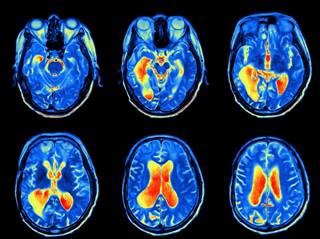

뇌의 활동을 측정하는 ‘기능성 자기공명 영상장치(fMRI)’ 안에 사람을 눕혀놓고 4초 동안 초콜릿을 보여준다. 이어 4초 동안 초콜릿의 가격을 보여준다. 그러고 나서 구매 여부를 결정하는 ‘예’ 또는 ‘아니오’ 단추를 누르도록 시킨다. ‘예’ 단추를 누른 사람은 초콜릿을 보는 순간 ‘쾌락의 중추’라고 불리는 영역이 강하게 활성화된다. 그가 가격표를 볼 때는 이 가격에 초콜릿을 살지 말지를 결정하는 짧은 순간 ‘이성적인 뇌 영역’이 활발하게 움직인다. ‘아니오’ 단추를 누른 사람은 살지 말지를 결정할 때 ‘이성적인 뇌 영역’이 활성화되지 않는다.